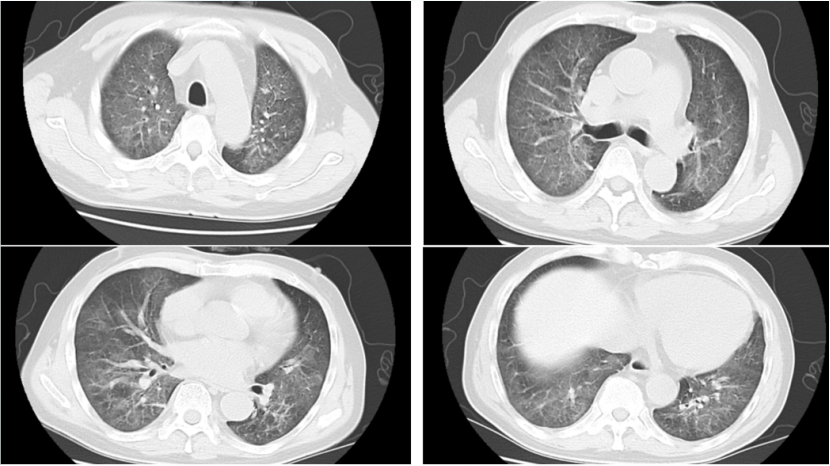

病例2:肾移植术后半年,发热3天。影像学表现并不严重(图10)。入院后完善NGS,耶氏肺孢子菌序列数330000。入院后即予SMZ+卡泊芬净+甲泼尼龙治疗,但病情仍然加重,入院10天转ICU,影像学持续进展(图11)。患者入ICU后NGS结果回报耶氏肺孢子菌序列数843433周后死亡。

10  患者入院胸部CT

11  患者病程中胸部CT变化情况